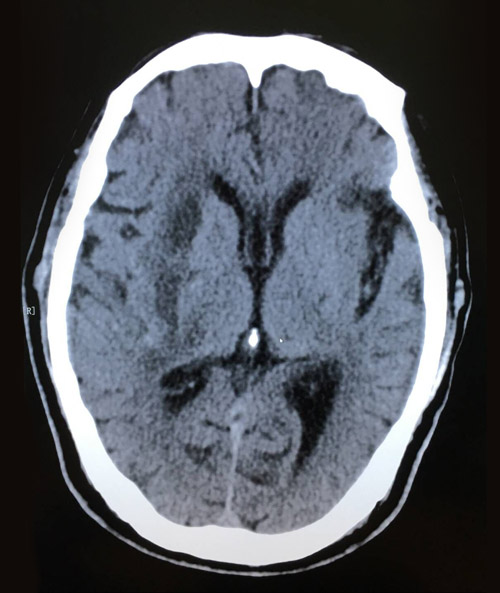

术后影像:脑出血引流术后,几乎看不到血肿残余